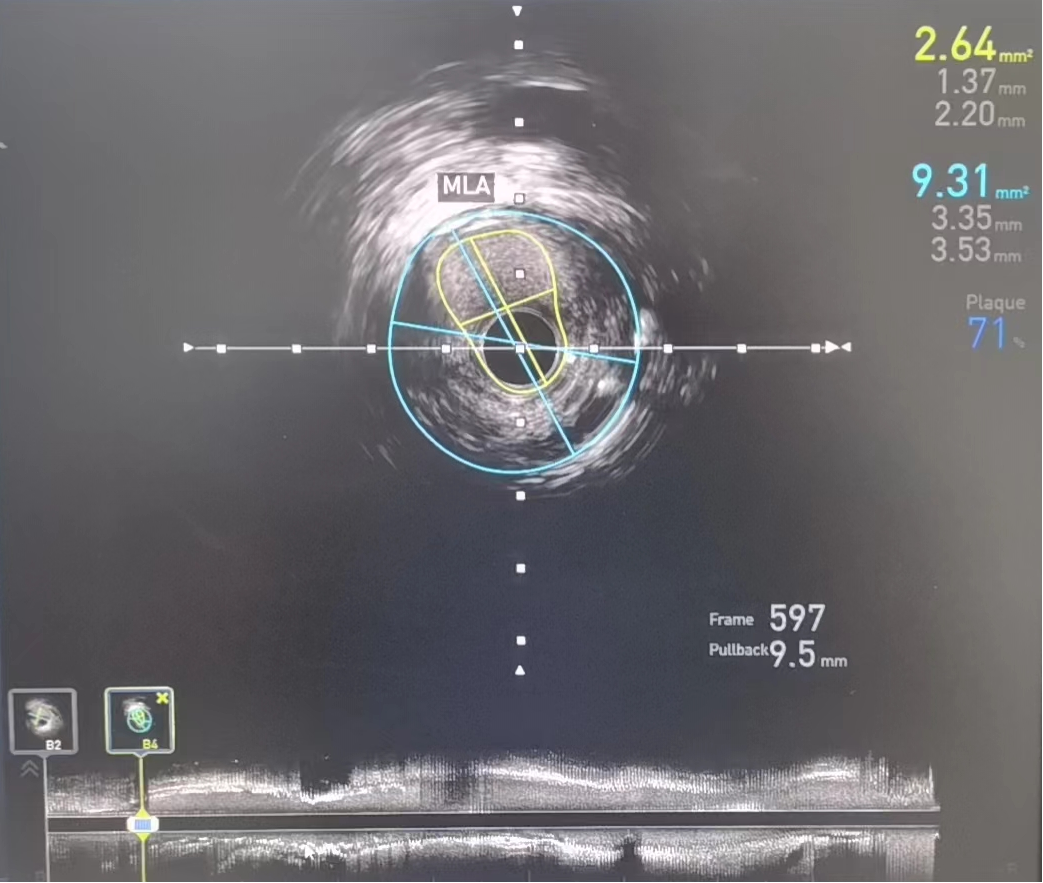

术前:IVUS-前降支管腔中段严重狭窄,最小管腔面积仅2.64mm2

IVUS检查提示右冠中段支架以远病变加重,右冠原支架管腔畅通,经IVUS测量得出病变处MLA(管腔最小横截面积)2.64mm2,结合心电图缺血判断,该病变为患者心绞痛发作罪犯病变,对病变处实施介入治疗。